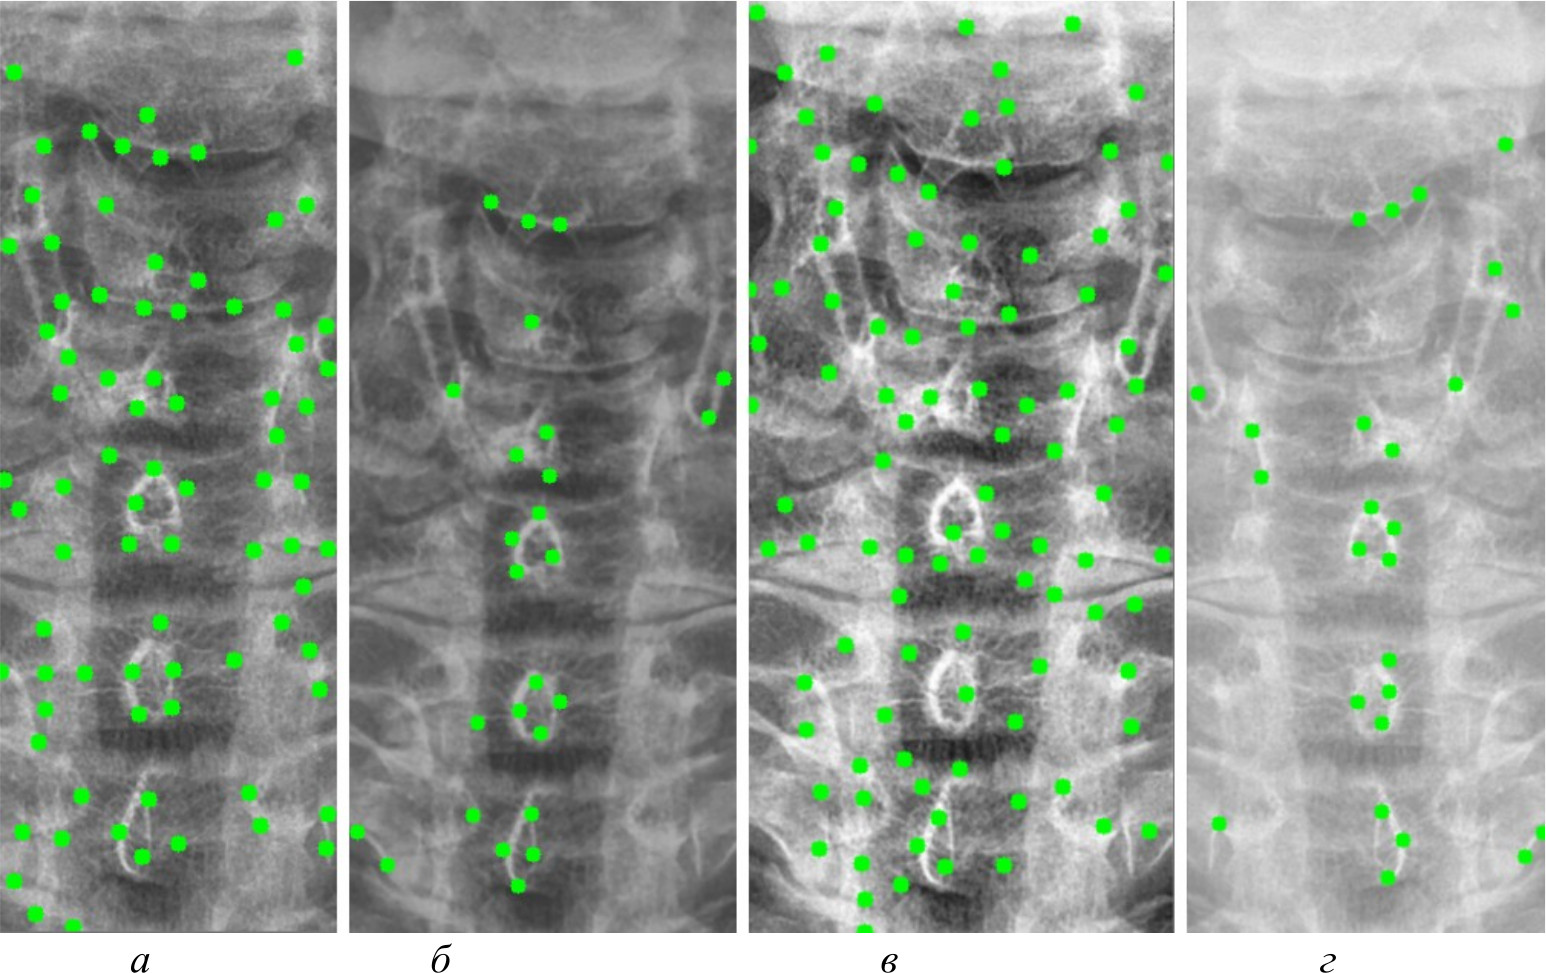

На рис. 4, 5 и 6 представлены результаты работы детектора Харриса, алгоритма Shi-Tomasi и SIFT при различных методах предварительной обработки изображений.

Рис. 4. Результаты работы детектора Harris на изображении, полученном при помощи специализированного программного обеспечения (а); результаты работы детектора Harris при методе адаптивной эквализации гистограммы (б); результаты работы детектора Harris при методе стандартной эквализации гистограммы (в); результаты работы детектора Harris при методе гамма-коррекции (г)

Рис. 5. Результаты работы алгоритма Shi-Tomasi на изображении, полученном при помощи специализированного программного обеспечения (а); результаты работы алгоритма Shi-Tomasi при методе базового отображения в Python (б); результаты работы алгоритма Shi-Tomasi при методе базового отображения Python с применением медианного фильтра (в); результаты работы алгоритма Shi-Tomasi при методе адаптивной эквализации гистограммы (г); результаты работы алгоритма Shi-Tomasi при методе стандартной эквализации гистограммы (д); результаты работы алгоритма Shi-Tomasi при методе гамма-коррекции (е)

Рис. 6. Результаты работы алгоритма SIFT на изображении, полученном при помощи специализированного программного обеспечения (а); результаты работы алгоритма SIFT при методе адаптивной эквализации гистограммы (б); результаты работы алгоритма SIFT при методе стандартной эквализации гистограммы (в)